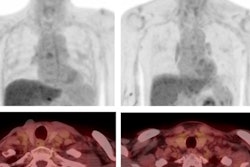

Cramer's group investigated the effects of lung cancer screening in this population, comparing both incidence of lung cancer in head and neck cancer survivors compared with those who had not had the disease and the performance of low-dose CT versus chest x-ray for identifying malignancy.

Of these 171 cancer survivors, 82 were subsequently screened with low-dose chest CT and 89 with chest x-ray. Not surprisingly, head and neck cancer survivors had higher rates of lung cancer compared with those who had not had the disease -- 2.5 times higher.

The investigators also discovered that CT found more secondary lung cancers than chest x-rays, at 2,610 cases per 100,000 person years (i.e., the number of people in the study and the time each person spends in the study) compared with 1,594 cases per 100,000 person-years. As well, those screened with low-dose CT had a higher overall survival rate compared to those screened with chest x-ray, at 7.1 years versus 6.7 years.